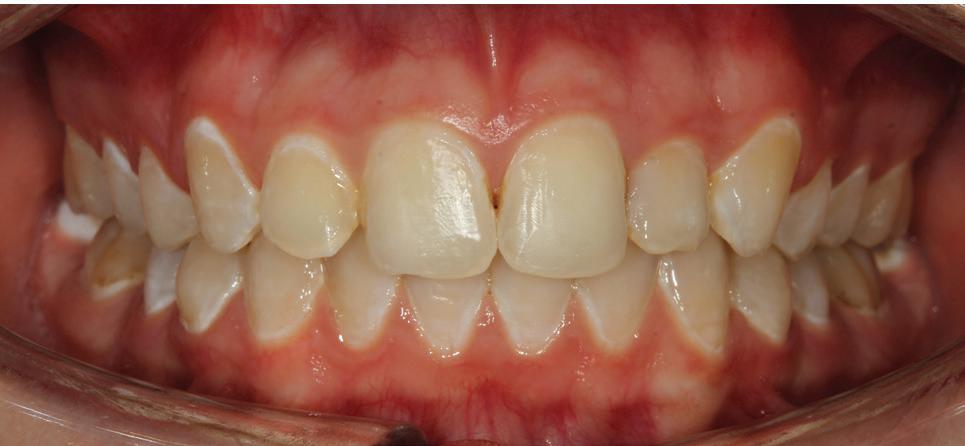

Estelite Asteria (Tokuyama)One of my favourite composite resin materials is Asteria which is a light-cured radiopaque composite for universal use. It considerably simplifies multilayer techniques yet delivers outstanding aesthetics with excellent polishability. Unlike mul tilayer techniques used with conventional composites, Asteria uses only 2 layers for optimal results without compromising aesthetics. The microstructure of the material produces a light diffusion that helps blend in with the natural tooth structure. The chameleon like nature of the material allows a blending of the materials to natural tooth structure and it allows excellent polishability which retains its lustre over time.